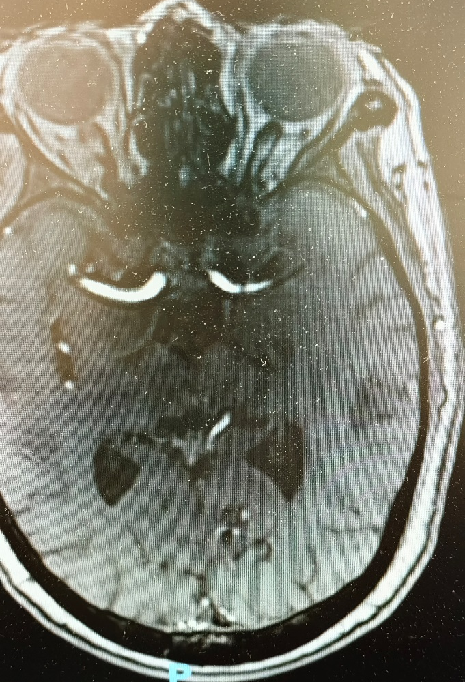

既往病史影像留存:

导丝怎么扩【载药时代 球扩天下】NOVA DES®颅内药物洗脱支架在大脑中动脉重度狭窄中的应用两例!_https://www.jmylbn.com_新闻资讯_第3张

导丝怎么扩【载药时代 球扩天下】NOVA DES®颅内药物洗脱支架在大脑中动脉重度狭窄中的应用两例!_https://www.jmylbn.com_新闻资讯_第4张

高分辨磁共振

重要影像结论:颅内多发陈旧性梗塞灶,左侧颈内动脉起始处;左侧大脑中动脉M1段可见重度狭窄。